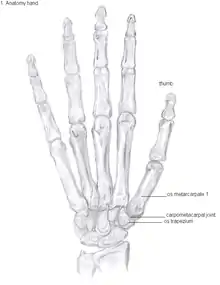

Anatomy

The TMC joint is a synovial joint between the trapezium bone of the wrist and the metacarpal bone at the base of the thumb. This joint is a so-called saddle joint (articulatio sellaris), unlike the CMC joints of the other four fingers which are ellipsoid joints.[17] This means that the surfaces of the TMC joint are both concave and convex.

The TMC joint is stabilized by 16 ligaments.[19] Of these ligaments, the deep anterior oblique ligament, also known as the palmar beak ligament, is considered to be the most important stabilizing ligament.[20]

Showing the bones of the hand